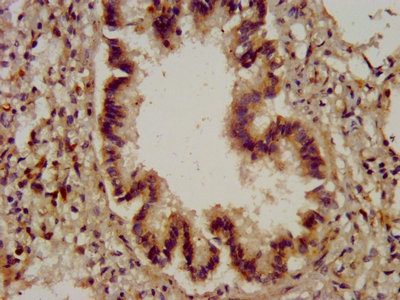

IHC image of CSB-PA006323LA01HU diluted at 1:200 and staining in paraffin-embedded human lung tissue performed on a Leica BondTM system. After dewaxing and hydration, antigen retrieval was mediated by high pressure in a citrate buffer (pH 6.0). Section was blocked with 10% normal goat serum 30min at RT. Then primary antibody (1% BSA) was incubated at 4°C overnight. The primary is detected by a biotinylated secondary antibody and visualized using an HRP conjugated SP system.